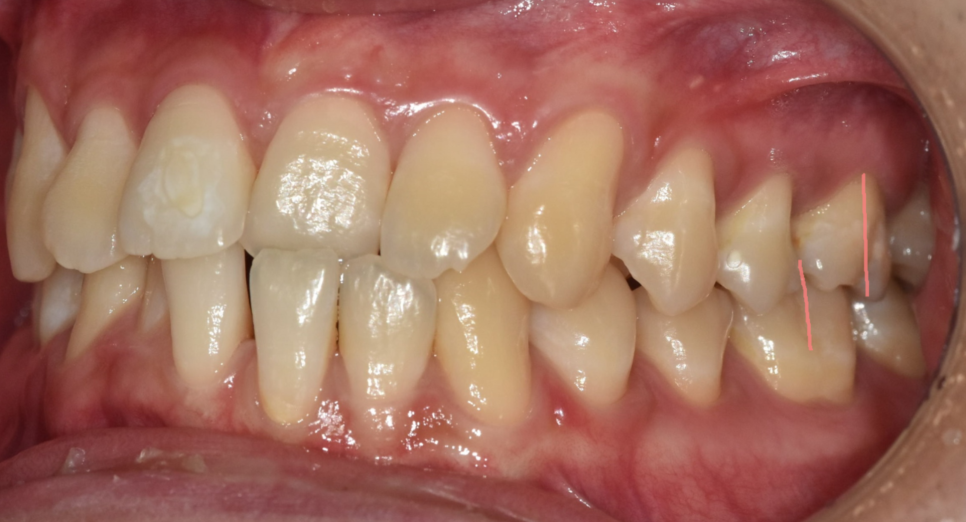

다행히 교합은 정상이었기 때문에

이럴 경우는 앞니 배열을 개선하면 치료가 종결됩니다.

기간도 1년 정도

상대적으로 짧게 소요됩니다.

아래 앞니는 뒤로 보내고

안쪽으로 들어간 윗니는 나오면서

전체 배열 정리가 되겠네요.

거꾸로 물리는 반대교합이 해소되면

웃을 때 답답한 인상이 개선됩니다.

벌어진 아래 앞니도

공간이 사라지면서 심미 회복까지 이루어지겠네요